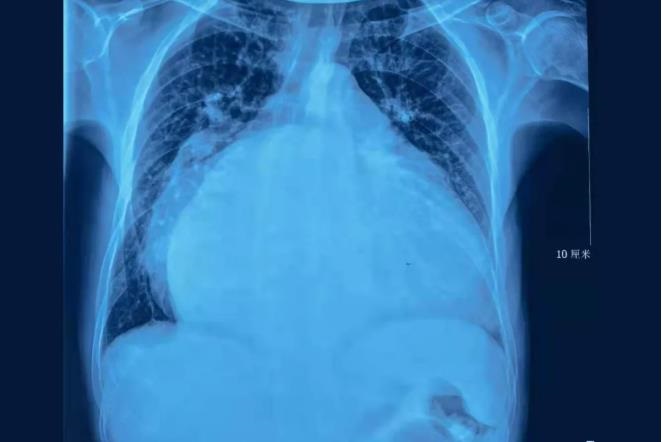

50岁男子心脏直径接近20厘米

状如篮球

塞满整个胸腔

严重挤压双肺等脏器

心外科权晓强主任医师接诊后,完善相关检查,当他拿到李先生的胸片后,简直不敢相信自己的眼睛:整个胸腔,全是心脏!

“这就是‘篮球心’,心功能很差,必须尽快手术!”权晓强主任医师说道。